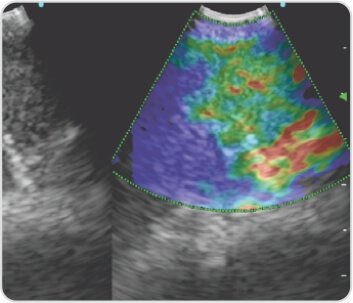

الشكل 5: حجم العقدة الليمفاوية العقدة المجاورة للرغامى (4R)

الشكل 6: تصوير العقدة المجاورة للرغامى - العقدة من النوع 2